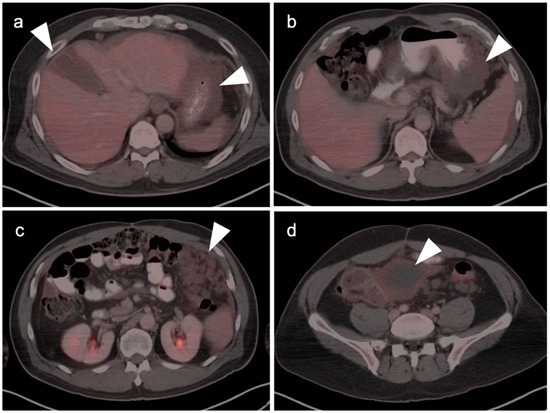

4. Hepatocellular Carcinoma